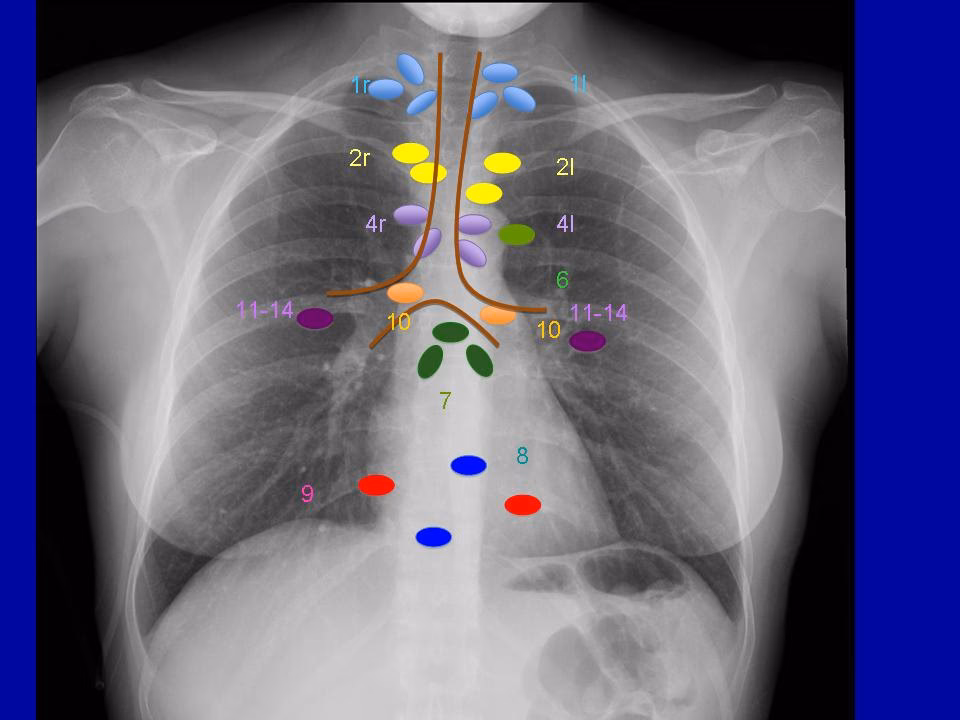

Pruebas de Imagen: Una Ventana al Interior del Tórax

Las técnicas de imagen son esenciales para visualizar, medir y caracterizar los ganglios afectados. Cada prueba ofrece información diferente y complementaria.